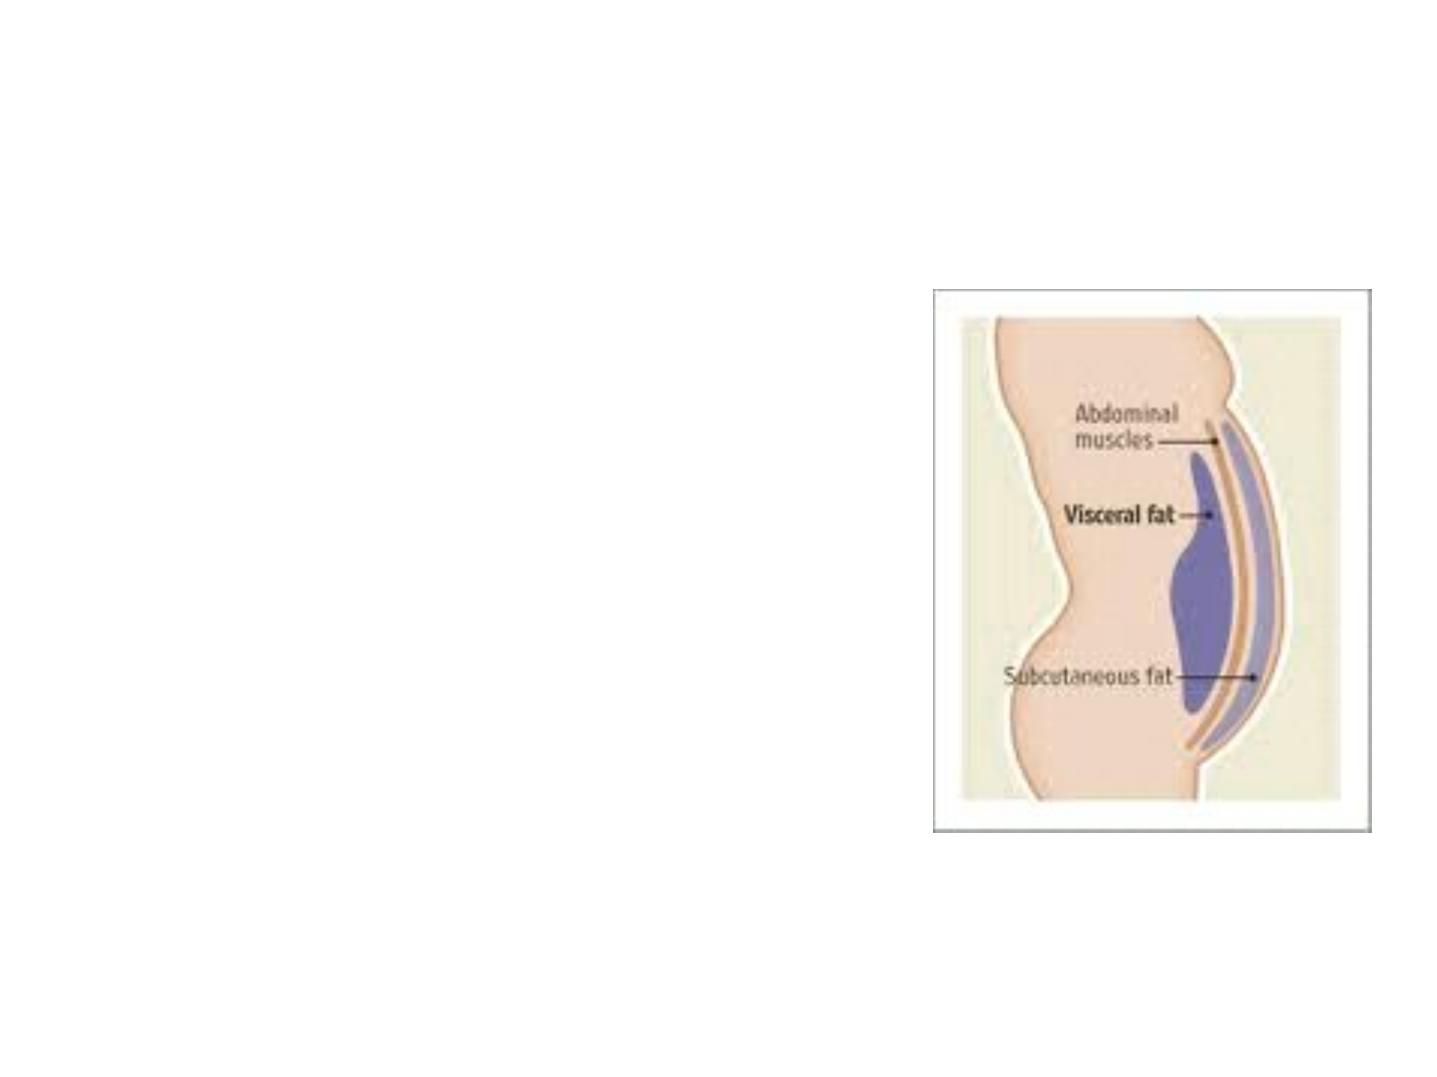

White Adipose Tissue

• It is the main type of adipose tissue

and can be found in subcutaneous

regions, surrounding visceral

organs and in the face

• Contains large unilocular lipid

droplets

• Differs between subcutaneous and

visceral

• It is an active endocrine organ that

regulates

- Insulin sensitivity and lipid

metabolism

7

MEDICAL APPLICATION

With its increased amounts of white adipose tissue, obesity is

characterized by a state of chronic mild inflammation. Cytokines and

other factors released from visceral fat are being investigated for links to

the inflammation-related disorders associated with obesity such as

diabetes and heart disease.